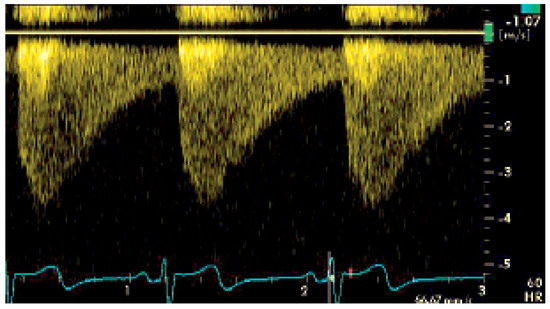

Fallbeschreibung. Ein 10jähriger Knabe wurde zur Abklärung eines Systolikums bei unauffälliger Anamnese und insbesondere uneingeschränkter körperlicher Belastbarkeit vorgestellt [...]